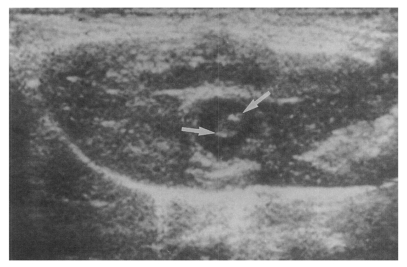

Sonography showed no dilatation of the bile duct confluence in the normal control group (Fig. 3). Sonograms showed moderate or marked dilatation of the bile duct confluence in the primary infection control group, the secondary infection control group, and the reinfection II group (Fig. 4, Table 2). A small number (1 of 7 in all groups) of animals showed mild dilatation of bile duct confluence in these groups (Fig. 5, Table 2). Dilated extrahepatic bile ducts were also observed. In the reinfection I group and the infection following immunization group, the degree of dilatation of the bile duct confluence was usually moderate (in n = 4 and n = 5, respectively). Marked dilatation was less frequent in these groups (n = 2 in each group).

Fig. 4

Sonogram of a rat in the primary infection control group 4 weeks after C. sinensis infection, showing marked dilatation of the bile duct confluence (arrows) with high echogenicity, reflecting worm burden and desquamated materials.

Fig. 5

Sonogram of a rat in the primary infection control group 4 weeks after C. sinensis infection, showing mild dilatation of the bile duct confluence (arrows).